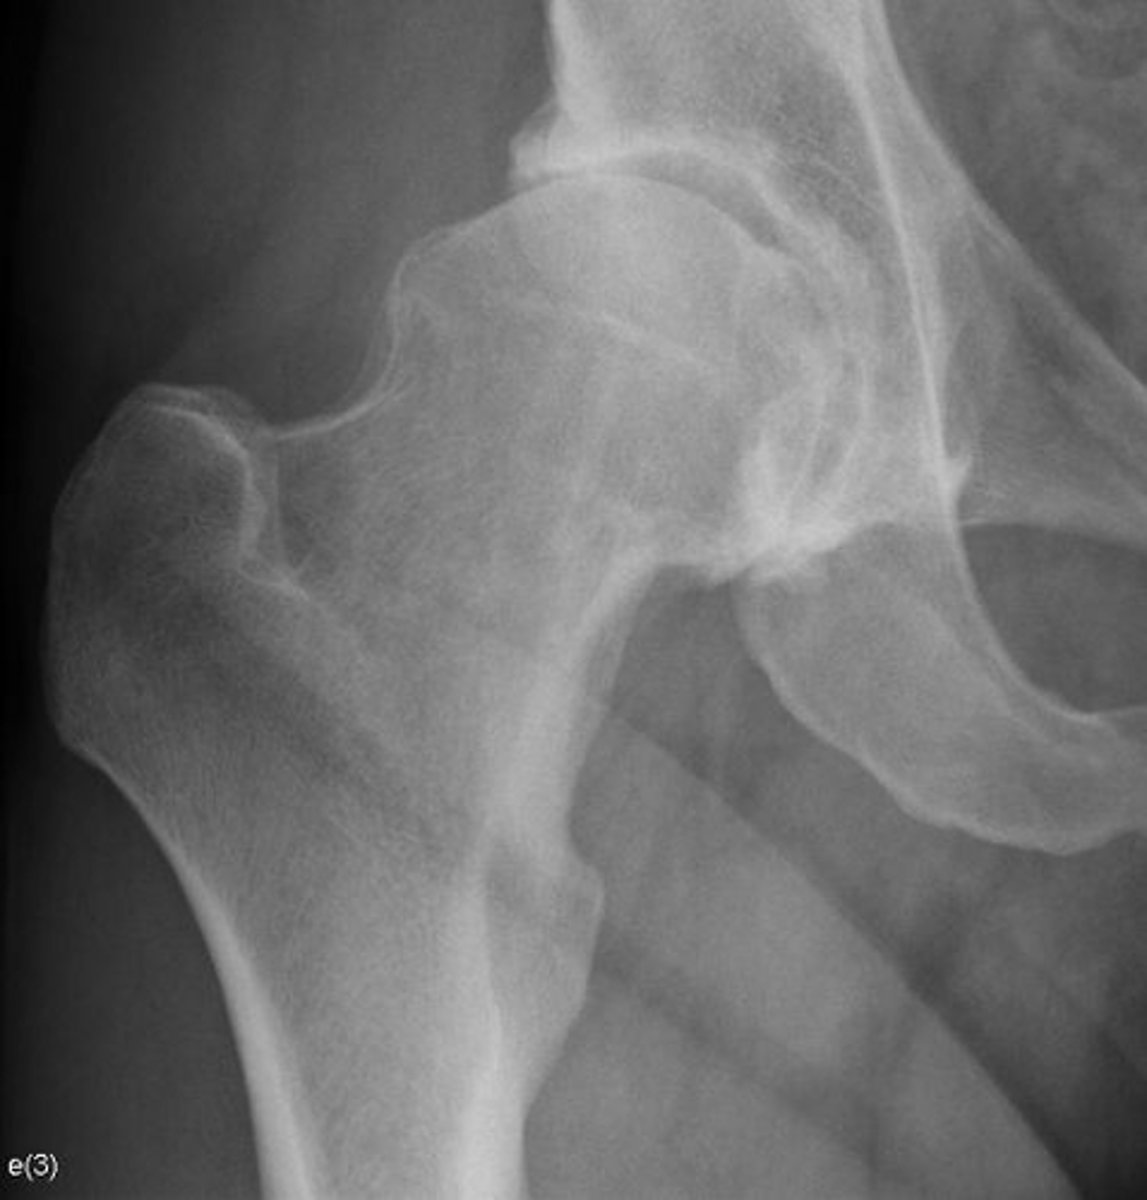

Right hip

Right femoroacetabular joint

Yes

Joint space narrowed?

Non-uniform

Uniform/non-uniform narrowing

No

Periarticular erosions

Osteophytes

Subchondral cysts

Subchondral sclerosis

Periarticular osteopenia

Soft tissue swelling

Intra-articular calcification

Joint ankylosis

Extra-articular calcification/osseous bodies

Subluxation

Dislocation/diastasis

Bilateral

Bilateral/unilateral

Degenerative

Category of joint disease

Osteoarthrosis

Most likely diagnosis?

Orthopedic referral

Next step?

- Collapse

- Step-off deformity

- More fragmentation

How can you differentiate this from avascular necrosis?